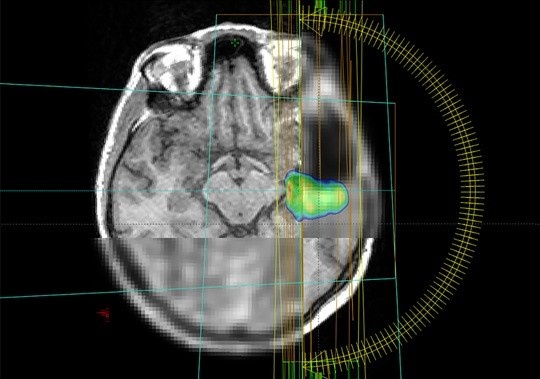

Glioblastome sind seltene, aber besonders aggressive Hirntumore. Häufig werden sie mit einer Strahlentherapie behandelt. Ein internationales Forschungsteam unter Leitung des Universitätsklinikums Freiburg untersucht nun in der Studie MATTO-GBM, wie der Tumor mit maximaler Intensität bestrahlt und umliegendes, gesundes Gewebe geschont werden kann. Dabei setzen die Forschenden auf eine erweiterte Bildgebung und eine Unterstützung durch Künstliche Intelligenz bei der Bildanalyse. Das Projekt wird von der Europäischen Union im Rahmen des Horizon 2020-Programms über drei Jahre mit 1,2 Mio. Euro gefördert.

Statt wie bisher meist nur Bilder aus dem Magnet-Resonanz-Tomografen (MRT) zu verwenden, nutzt das Forschungsteam aus Spanien, Deutschland und Österreich in der aktuellen Studie auch auf die Positronen-Emissions-Tomografie (PET)-Bildgebung. „Wie wollen durch die Kombination aus MRT und PET die biologischen Eigenschaften der Tumore besser verstehen. Damit wird der Stoffwechsel im Tumor sichtbar und eine hochwirksame Bestrahlung besonders gefährlicher Tumoranteile möglich“, sagt die Physikerin Monserrat Carles Fariña, die sowohl in Valencia, Spanien, als auch am Universitätsklinikum Freiburg im Projekt aktiv involviert ist.

Ein weiterer Fokus der Studie liegt auf dem Einsatz von Künstlicher Intelligenz: Sie hilft, den Tumor auf den Bildern genauer zu definieren und vorherzusagen, wann und wo er möglicherweise wieder auftreten könnte. Ein großes Ziel der Forscher*innen ist die Schaffung eines frei zugänglichen digitalen Tools. Dieses soll es Krankenhäusern weltweit ermöglichen, die Therapie des Glioblastoms auf das individuelle Risikomuster von einzelnen Patient*innen abzustimmen und so die Lebensqualität der Betroffenen zu erhöhen. Das Projekt bringt Spezialisten aus den Bereichen Künstliche Intelligenz, Radioonkologie, Nuklearmedizin, Neuroradiologie, Medizinphysik, Neuropathologie und Neurochirurgie zusammen.